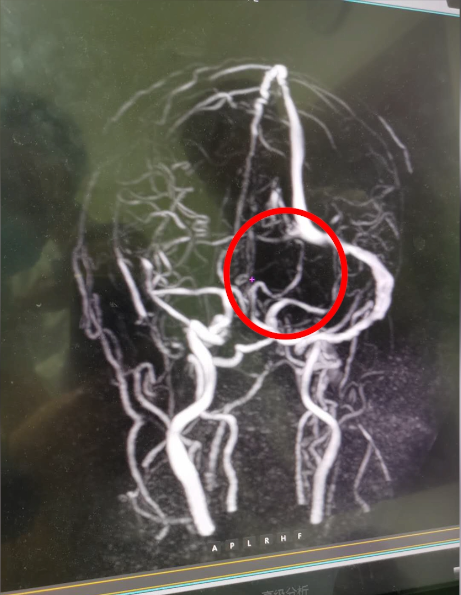

头晕呕吐在我们的生活中很常见,引起头晕呕吐的原因也很多。近日有一位脑囊虫病患收入我院,经过治疗症状刚有好转,又出现了头痛呕吐。我院高度重视,仔细检查排查后,确诊患者为左侧颅内静脉窦血栓形成。

头颅MRV检查发现血栓形成

该病在临床上并不多见,因此容易漏诊和误诊。患者经常被误诊为脑动脉性梗死、脑肿瘤、脑部感染等。CT核磁共振可看到间接征象,但直接征象主要依靠MR静脉成像(MRV)。